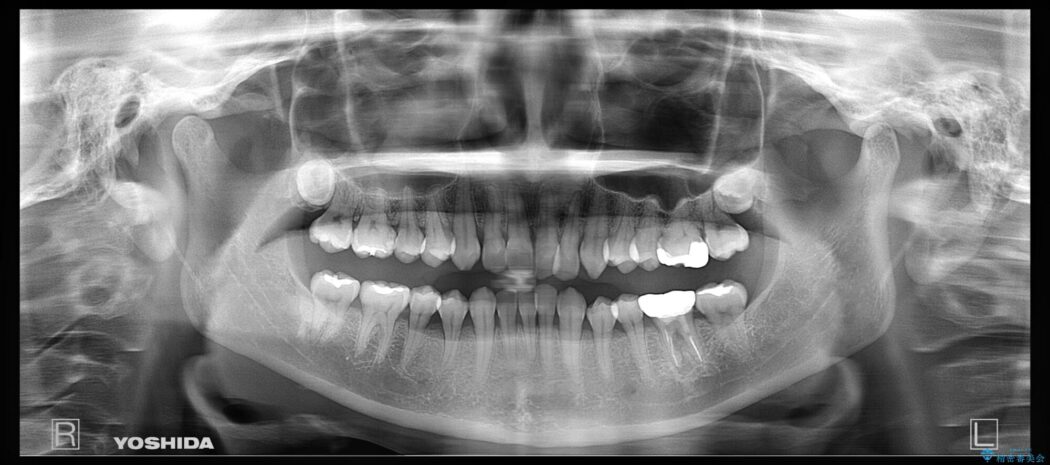

治療計画を立てる上で詳しく精密検査をしたところ、左下の6番目の歯につきまして治療が必要な状態であることが分かり、かぶせ物を外し、内部を確認しました。

結果としては深い部分で根が破折してしまっていました。

破折の処置としては基本的に抜歯が選ばれます。

悪くなっている歯の放置はできないと判断しましたので、患者様と様々な治療プランを相談した上で、最終的に該当の歯は抜歯をして噛み合わせを改善し、その後インビザラインでの矯正治療を行うこととしました。

当院では矯正治療をご希望される患者様には治療前に必ず精密検査を受けていただいております。

患者様本人に自覚のない状態であっても隠れて歯周病が進行していたり、根幹治療が必要になるといったケースがあります。

基本的に歯周病や虫歯に関する治療は矯正治療に移る前に完治させておくことが前提となります。

理由として、矯正装置装着後は清掃不良になりやすく、虫歯の進行が早まったり、歯を移動させることで歯周病や根尖病巣が悪化する可能性があるためです。